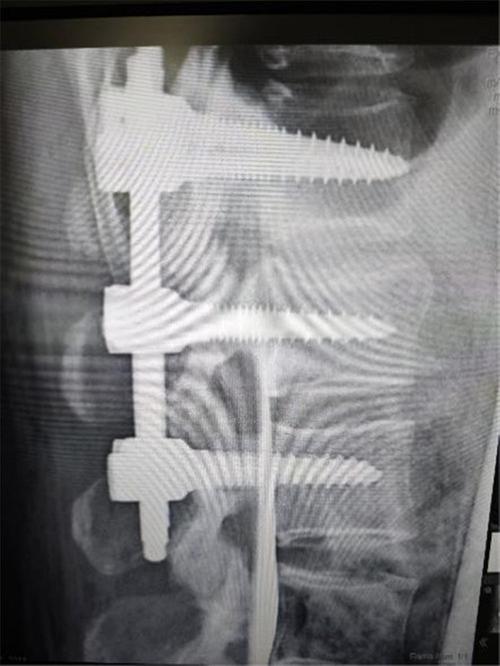

48歲的王女士近日因外傷入院,CT檢查結(jié)果顯示腰1椎體爆裂骨折,骨折累及前中柱,椎體后壁骨折塊突入椎管,壓迫硬膜囊??剖壹怪鶊F隊經(jīng)過深入討論,一致認(rèn)為該患者骨折屬于不穩(wěn)定性,若不及時治療,有極高的癱瘓風(fēng)險,應(yīng)盡量采用創(chuàng)傷較小術(shù)式早期手術(shù)結(jié)合術(shù)中椎管造影確保手術(shù)效果。

在骨科與手麻科團隊的緊密配合下,首次采用肌間隙入路技術(shù)成功為患者實施了手術(shù)治療。這一技術(shù)相較于傳統(tǒng)的后正中入路,利用多裂肌和豎脊肌之間的天然間隙,減少了對肌肉的牽拉,避免了腰背肌的醫(yī)源性損傷或壞死。術(shù)中出血量顯著減少,僅為80ml,遠低于傳統(tǒng)手術(shù)的200~300ml。術(shù)后,患者清醒且未出現(xiàn)腰痛、腰脹等不適癥狀。